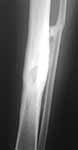

Wide segmental resection as it was a tumor, acute compression and proximal lengthening as shown (for the femur) at http://www.geocities.com/craveiro01/brodie01.htm

On the tibia you can resect as much as 8-10 cm without any vascular impairment. What we do is to control vascular flow with a oximeter on the great toe on the post operative period and if measurements are lower than on the opposite great toe, we decompress it until ppO2 is normal and do continuous compression.